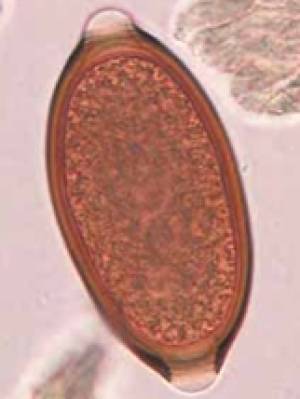

- Spulwürmer

- Toxocara canis (Hd)

- Tococara cati (Ktz)

- Toxocara leonina (Hd, Ktz)

- Kotflotation

- Indikation: Würmer, Giardien, Kokzidien

- Durchführung: Flotation in Zinksulfatlösung mit darüber liegendem Deckglas für 10 Minuten

- Sammelkotproben wesentlich aussagekräftiger, da Wurmeiern intermittierend ausgeschieden werden